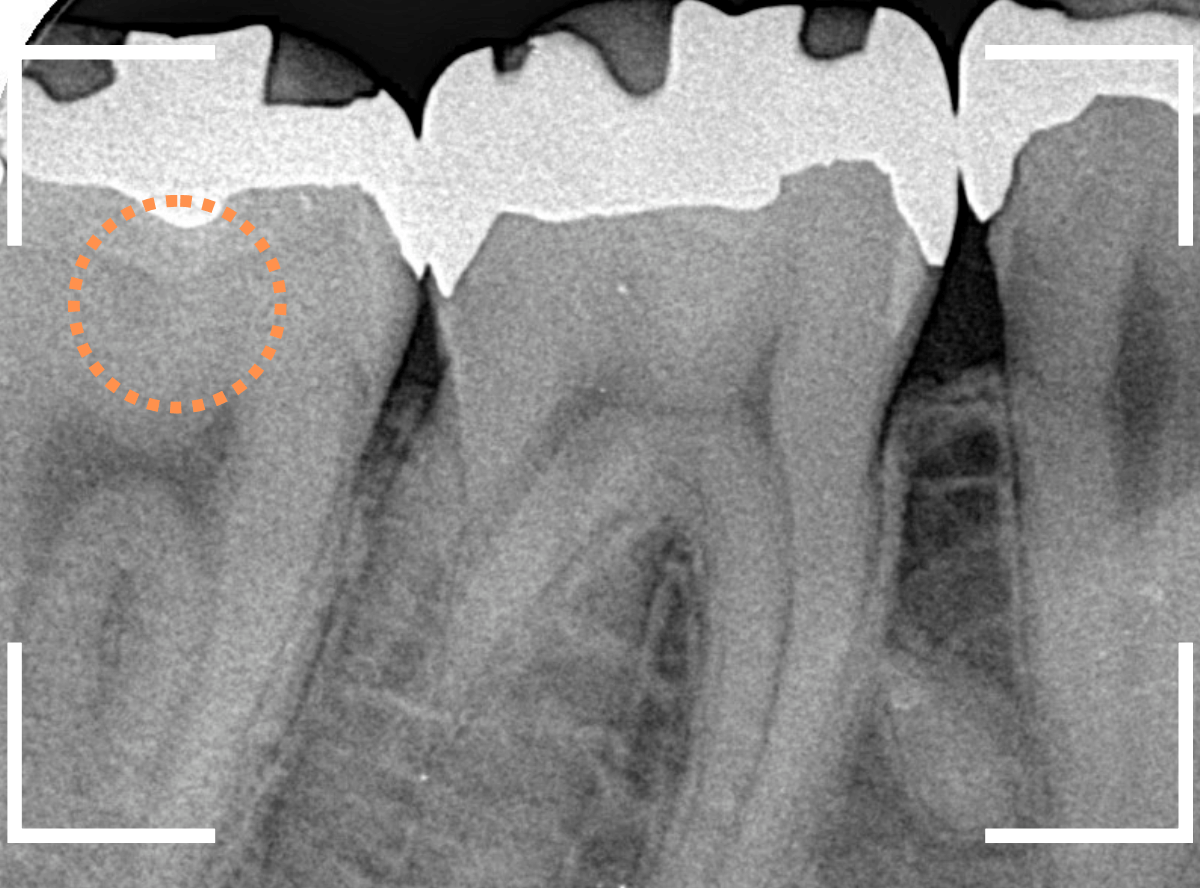

レントゲン写真で確認します。

〇部が当該の歯です。

症状もあるので、虫歯が深そうですが、全体がもやっとして、どこからどこまで虫歯なのかはっきりわかりません。

まれに、こんな時もあります。